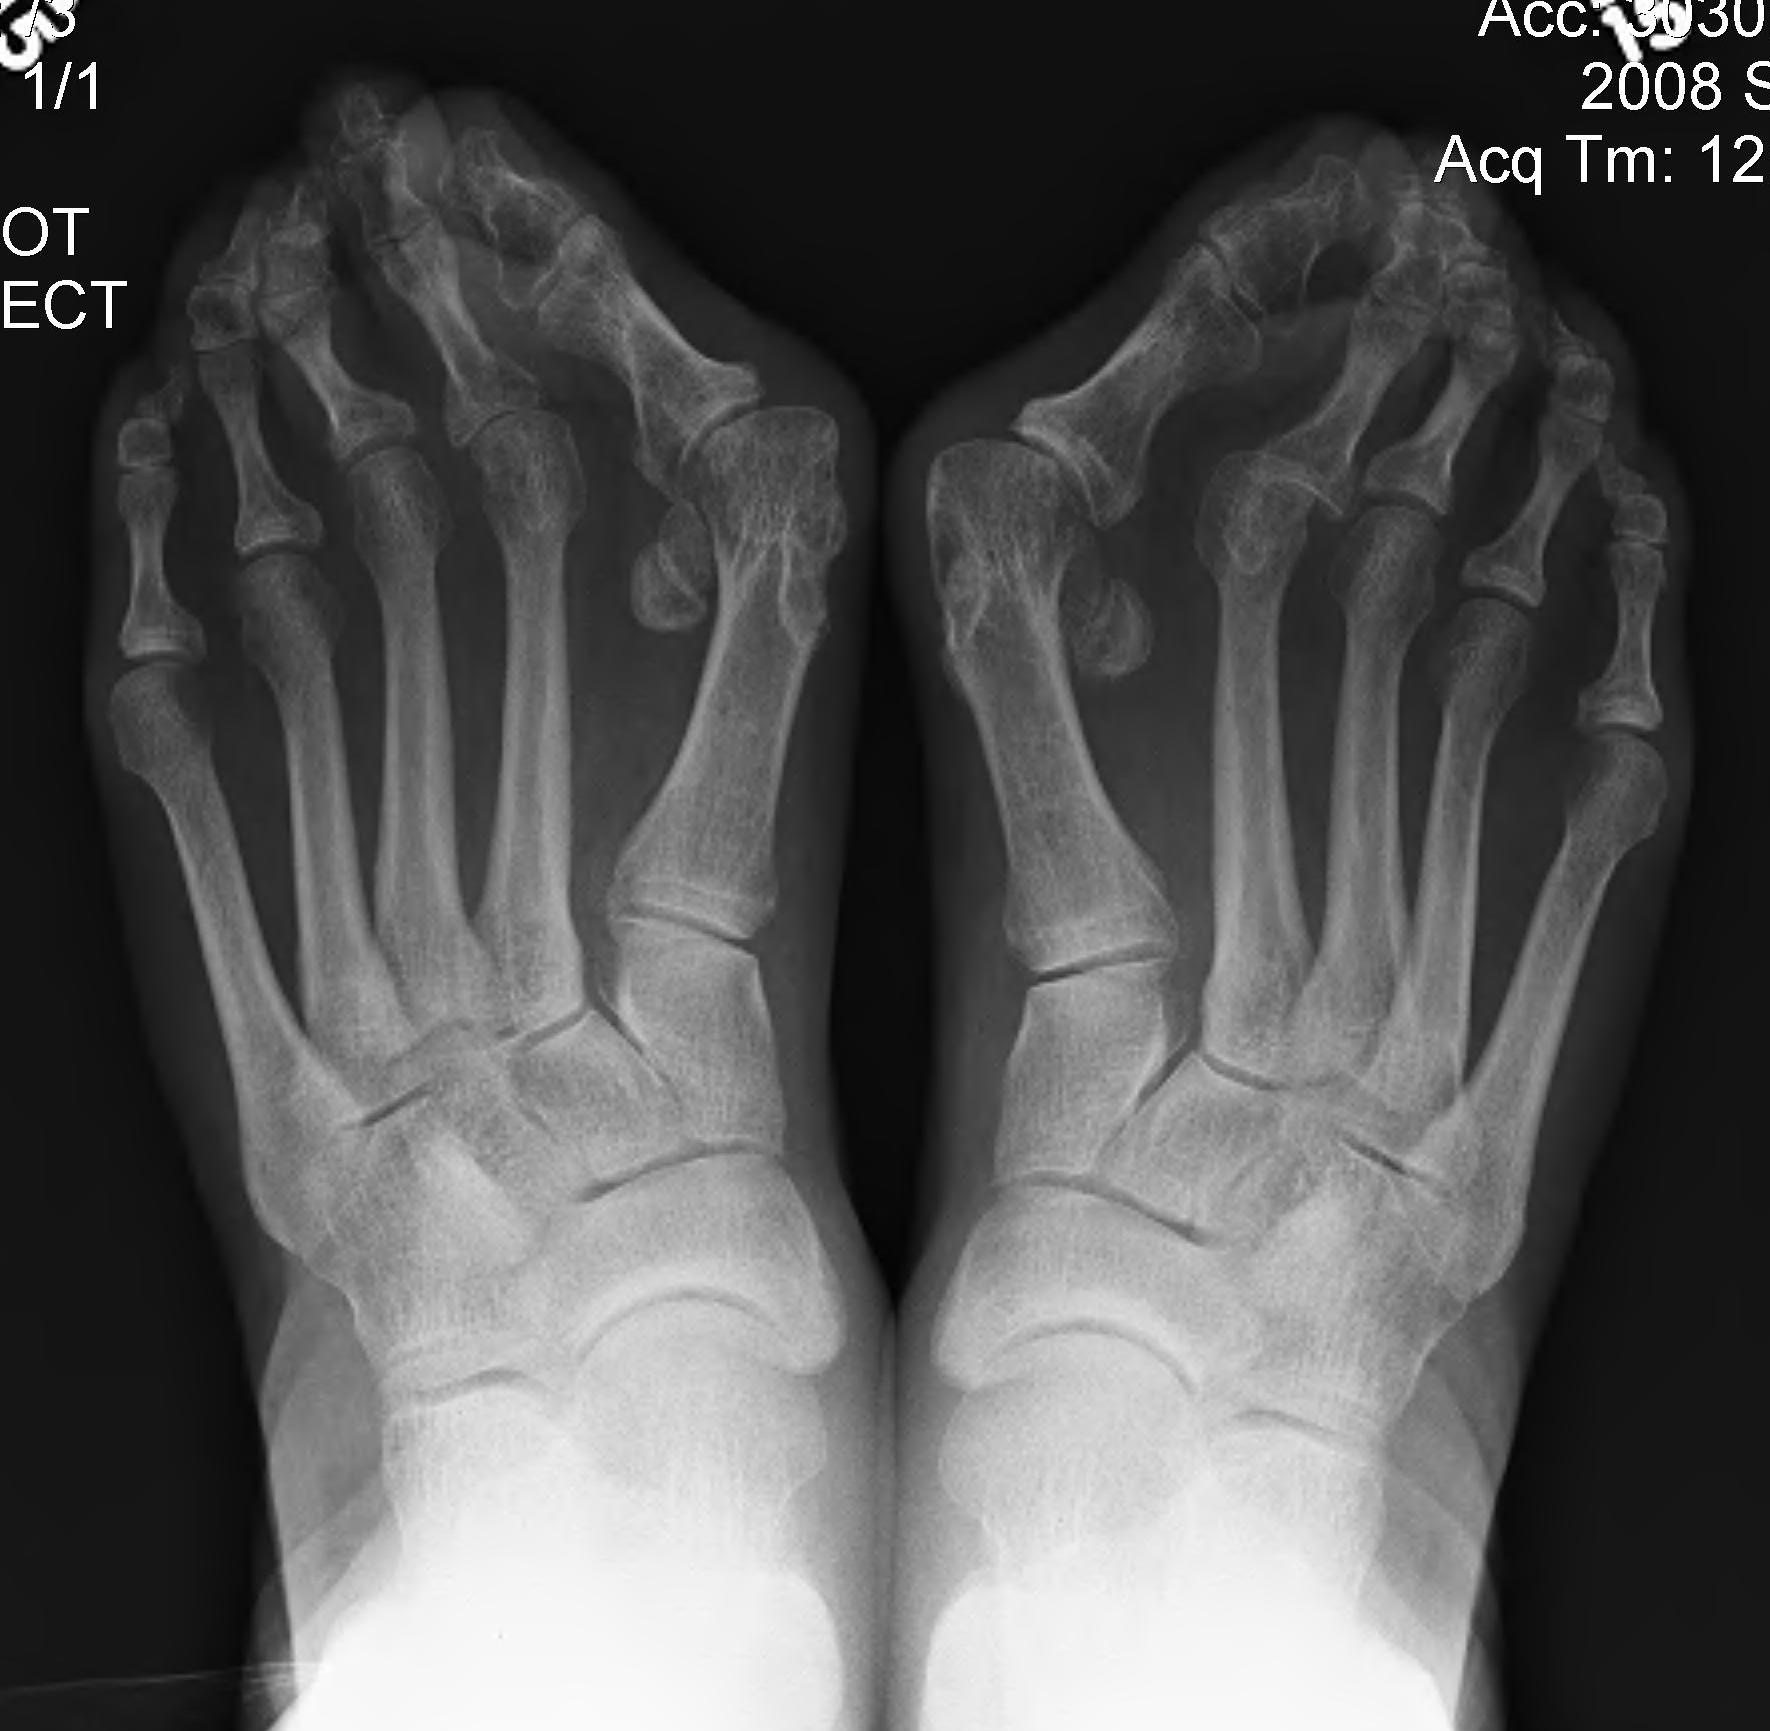

DefinitionHallux Valgus Severe

Bunion

- medial prominence of head of 1st MT

Hallux Valgus

- medial deviation 1st MT

- lateral deviation of great toe